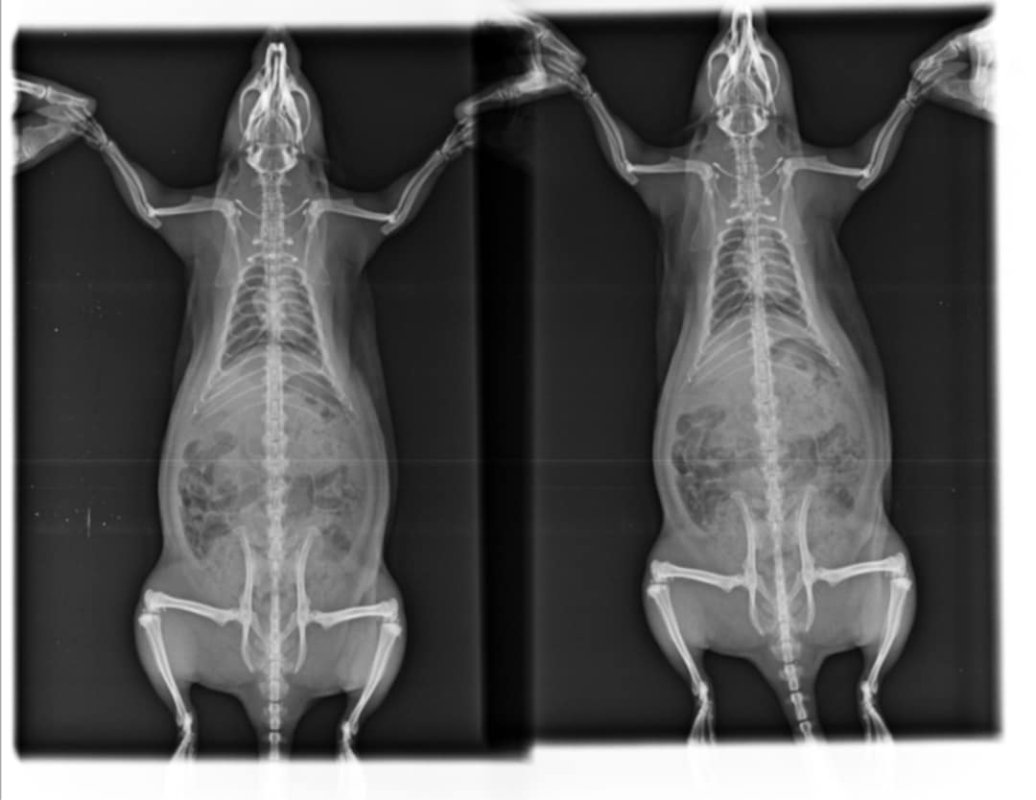

Radio du 12 mai:

Messenger_creation_405C0D98-340E-499F-B66E-C15ED85CE621.png.f4a641b99a04b2beb5ffee18ba1337e6.pngMessenger_creation_7D074FAC-7A52-4F75-B187-71C448B07FB3.png.1e0bb01bf8a2847b489760fa7057450f.png

Les radios sont pas terribles, pas très bien exposées ni assez centrées sur la cage thoracique et floues, du coup perso j'arrive pas à voir grand chose >< Mais bon tes vétos ont sans doute davantage l'habitude. Par contre je trouve aussi que le cœur est gros.